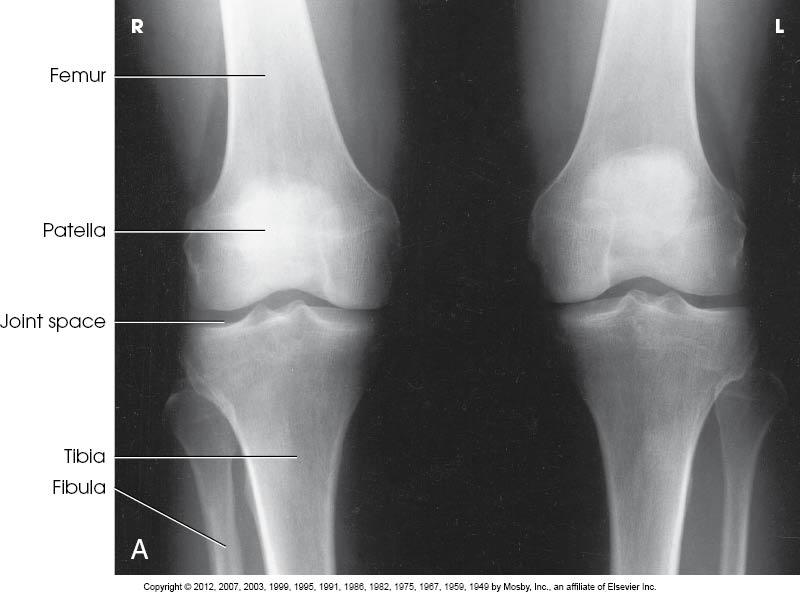

X Ray Knee Bilateral Ap Standing

Patient position patient is supine on the table with the knee and ankle joint in contact with the table leg is extend. The front to back or anterior posterior knee image can be made in both supine and standing positions fig. 2 malalignment can lead to excessive forces on parts of the joint and accelerate arthritic changes. The knee ap weight bearing view is a specialized projection to assess the knee joint distal femur proximal tibia and fibula and the patella.

The knee ap view is a standard projection to assess the knee joint distal femur proximal tibia and fibula and the patella. The long common names have been created via a table driven algorithmic process. Oa is a painful degenerative condition that can reduce your mobility and make daily tasks difficult to manage. You instead count the standing ap view as a third view and you report code 73562.

The 45 flexed pa standing view of the knee is a much more sensitive x ray showing early degenerative disease in the position of function. In supine position the x rays pass through the knee from anterior to posterior ap image. Xr knee bilateral ap and lateral w standing this field contains the loinc term in a more readable format than the fully specified name.